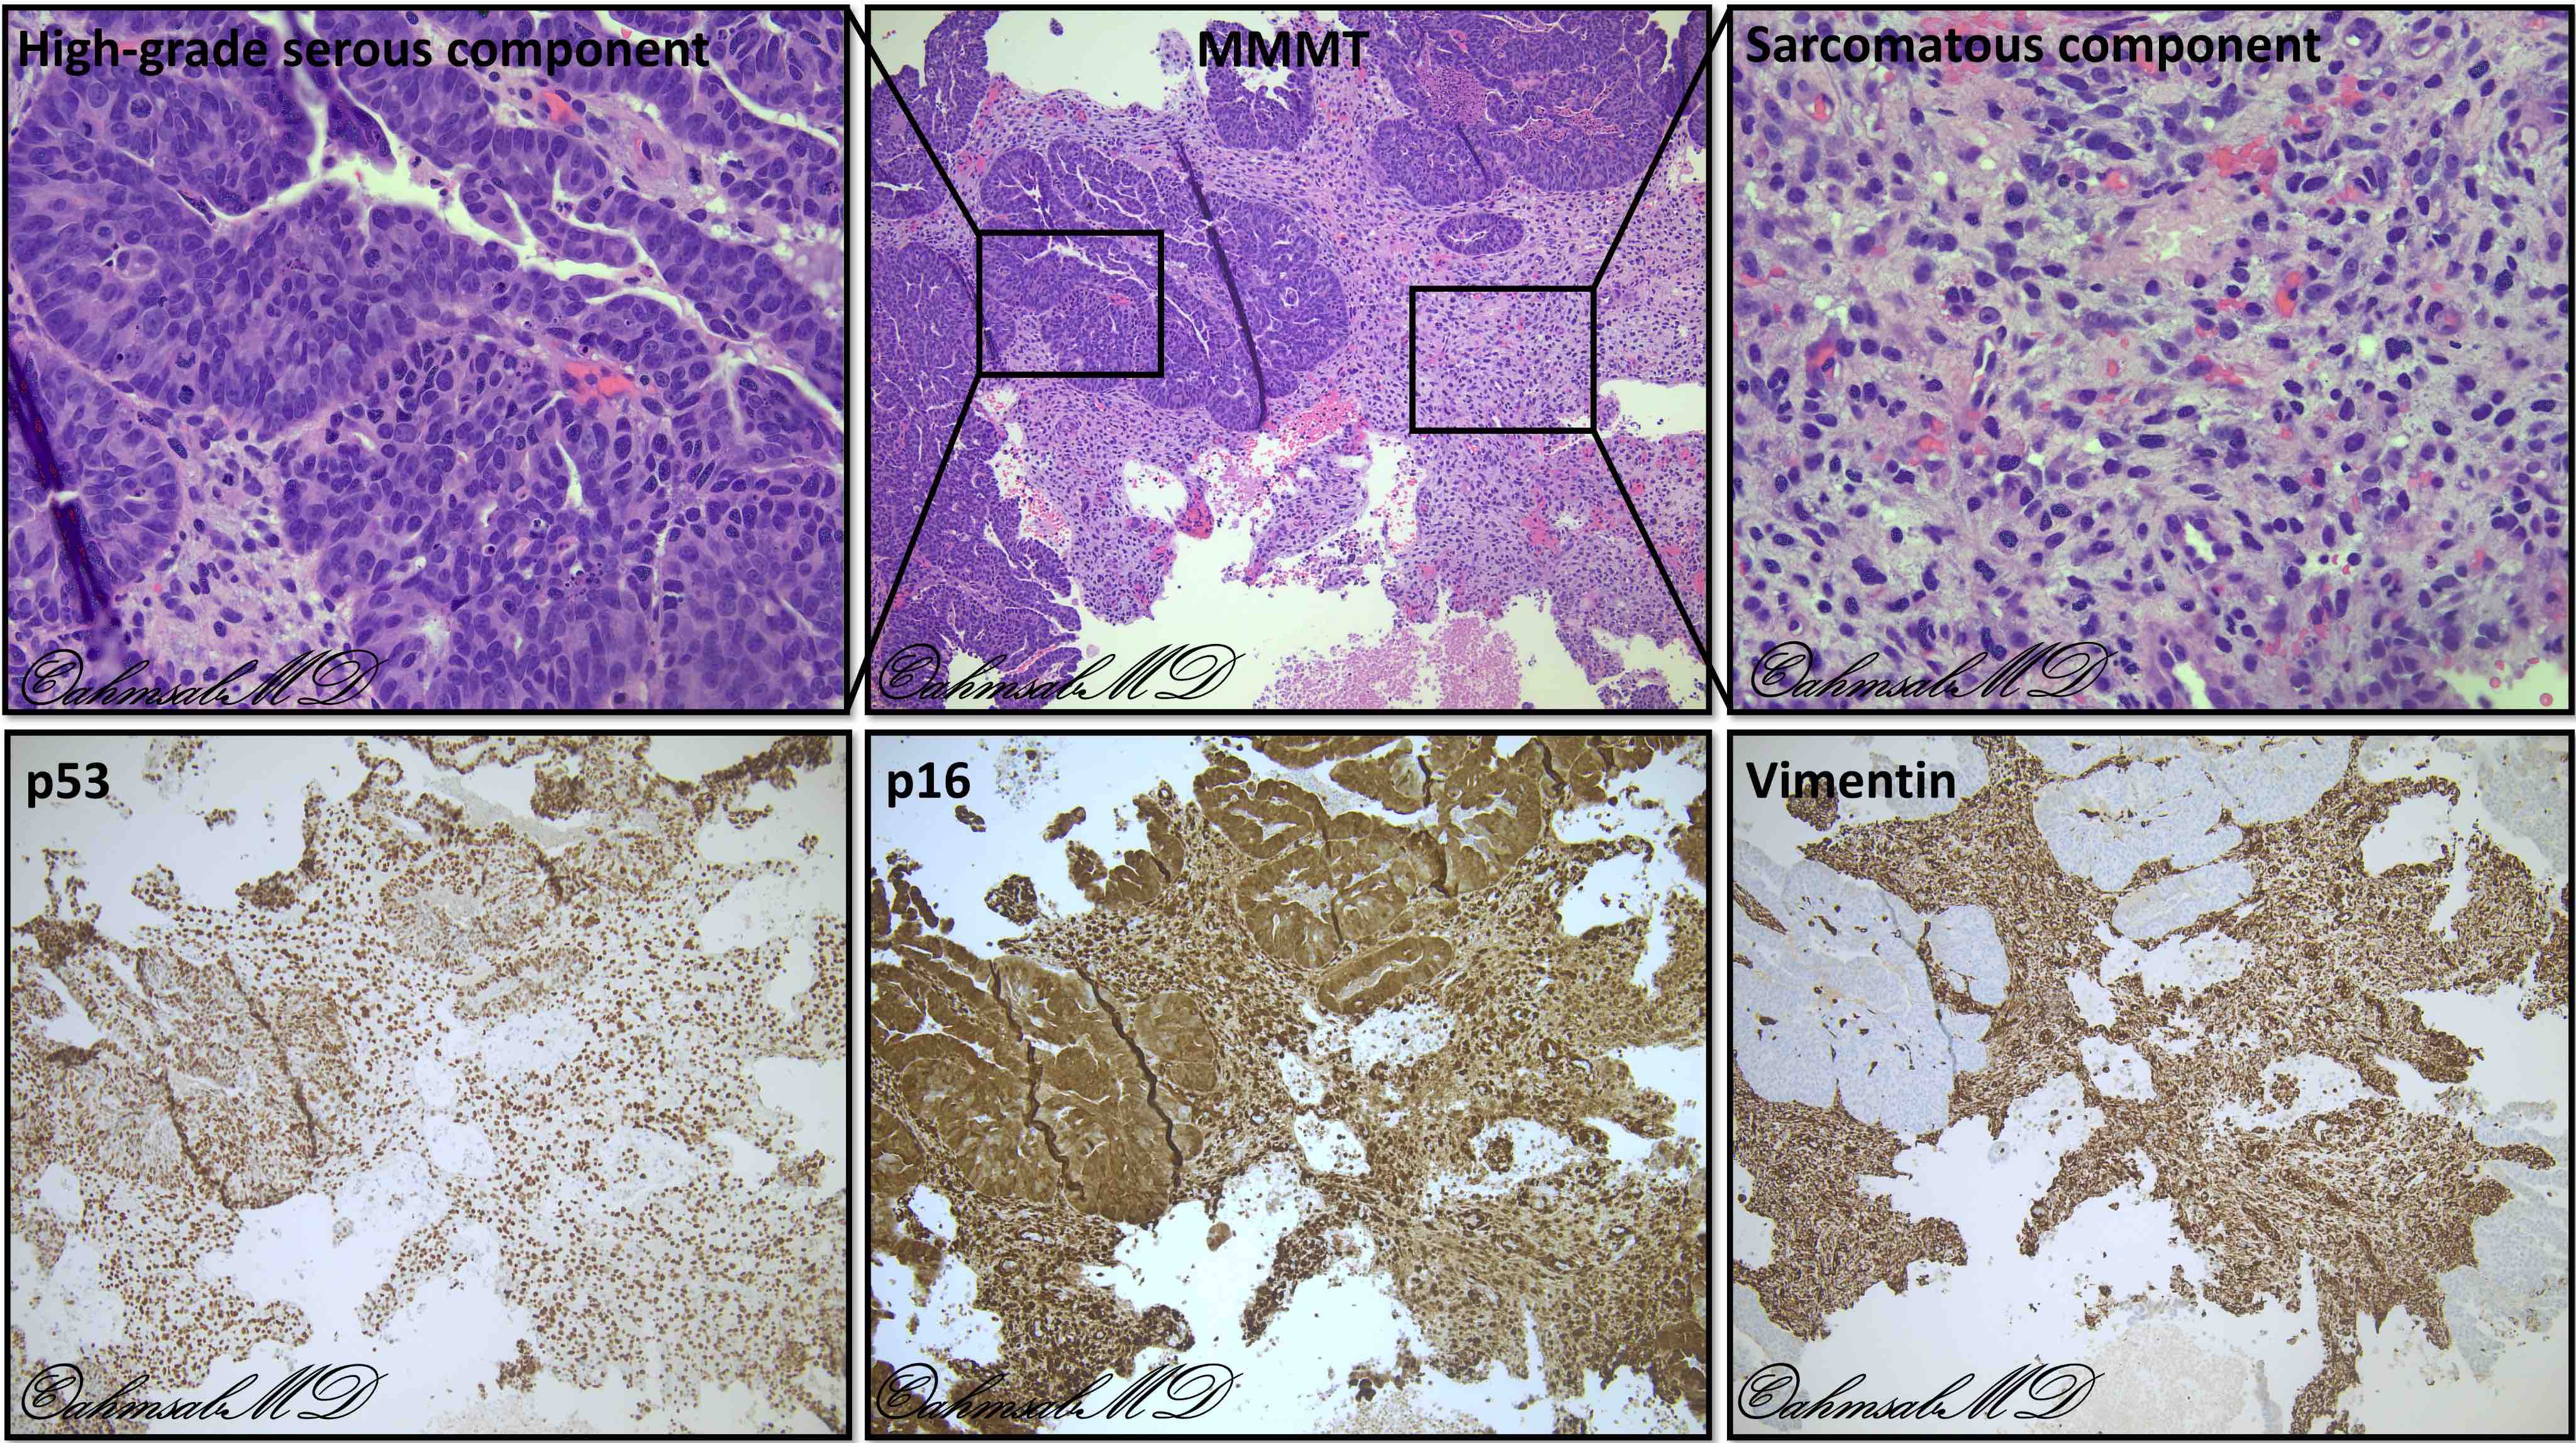

Microscopic (histologic) description

- Biphasic tumor with carcinomatous and sarcomatous elements, both high grade (Int J Gynecol Pathol 1990;9:1)

- Carcinomatous and sarcomatous components are juxtaposed

- Carcinomatous elements:

- Often high grade endometrioid or serous carcinoma, frequently admixed

- More uncommonly clear cell carcinoma

- 50 - 75% of cases have serous or mixed serous and high grade endometrioid carcinoma (Am J Surg Pathol 2007;31:1653)

- Hybrid morphology between endometrioid and serous carcinoma is frequent, as is undifferentiated carcinoma (Mod Pathol 2010;23:781)

- Sarcomatous elements:

- Often spindle and pleomorphic

- 50% contain heterologous elements (most commonly rhabdomyosarcoma and chondrosarcoma) (Am J Surg Pathol 2007;31:1653)

Microscopic (histologic) images

Positive stains

- Immunohistochemistry is not necessary to establish the diagnosis

- Can be useful to demonstrate heterologous differentiation (skeletal muscle)

- Carcinomatous component:

- PAX8, EMA, cytokeratin positive

- Both serous and high grade endometrioid carcinomas may show aberrant p53 expression (Int J Gynecol Pathol 2017;36:412)

- Endometrioid components can show ER, PR positivity

- Sarcomatous component:

- Often shows aberrant p53 expression (Int J Gynecol Pathol 2017;36:412)

- Rhabdomyosarcoma: desmin and myogenin

- Liposarcoma and chondrosarcoma: S100